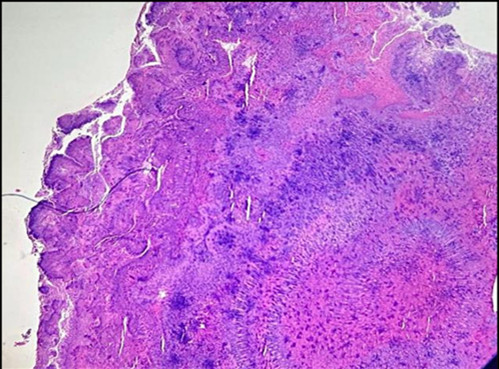

A 22-year-old female presented to the ENT outpatient department with right sided headache, nose block and recurrent upper respiratory tract infection for two months that was insidious in onset and intermediate in nature. Patient also complained of heaviness of head and frequent nasal discharge. she also gave a history of hemoptysis two weeks ago. Her general physical examination was normal. She had no other significant comorbidities. Local examination showed pink nasal mucosa and deviated nasal septum to left. Radiological examination (CT paranasal sinuses) showed polypoidal mucosal thickening in right maxillary and right anterior ethmoidal sinus, widening of right osteomeatal complex. Mild mucosal thickening of left frontal and bilateral ethmoid sinuses, suggestive of sinusitis was noted. Right inferior turbinate hypertrophy was also found. She was clinically diagnosed with deviated nasal septum to left and chronic sinusitis. After preoperative evaluation, patient underwent submucosal resection with micro-debrider assisted polypectomy and the representative tissue bits from right maxillary and ethmoidal sinus were sent for histopathological examination. Grossly, multiple grey white soft tissue bits altogether amounting to 1cc was received in histopathology. Microscopic examination showed fragments of tissues lined by respiratory pseudostratified ciliated columnar epithelium with dense chronic inflammatory cells in the underlying stroma (Figure 1 [Fig. 1]). Fungal organisms showing actinomycotic sulphur granules (Figure 2 [Fig. 2]). Dense basophilic filamentous organisms surrounded by eosinophilic clubs, known as Splendor hoeppli phenomenon, were noted within dense mixed inflammatory cells. Gram stain and Gomori methanamine silver stains were done. Gram stain showed Gram-positive intertwined branching filamentous organisms with radially arranged peripheral hyphae (Figure 3 [Fig. 3]). Gomori methanamine silver stain showed colony of filamentous micro-organisms which stained black (Figure 4 [Fig. 4]). Histopathology and special stains confirmed the diagnosis of actinomycosis. Patient was given intravenous antibiotics, cephalosporin for a week and given oral antibiotics for 3 months with periodic follow up. Patient is currently doing well with no evidence of recurrence or infection.

Figure 1: Respiratory epithelium with dense chronic inflammation in underlying stroma (H&E;10x)